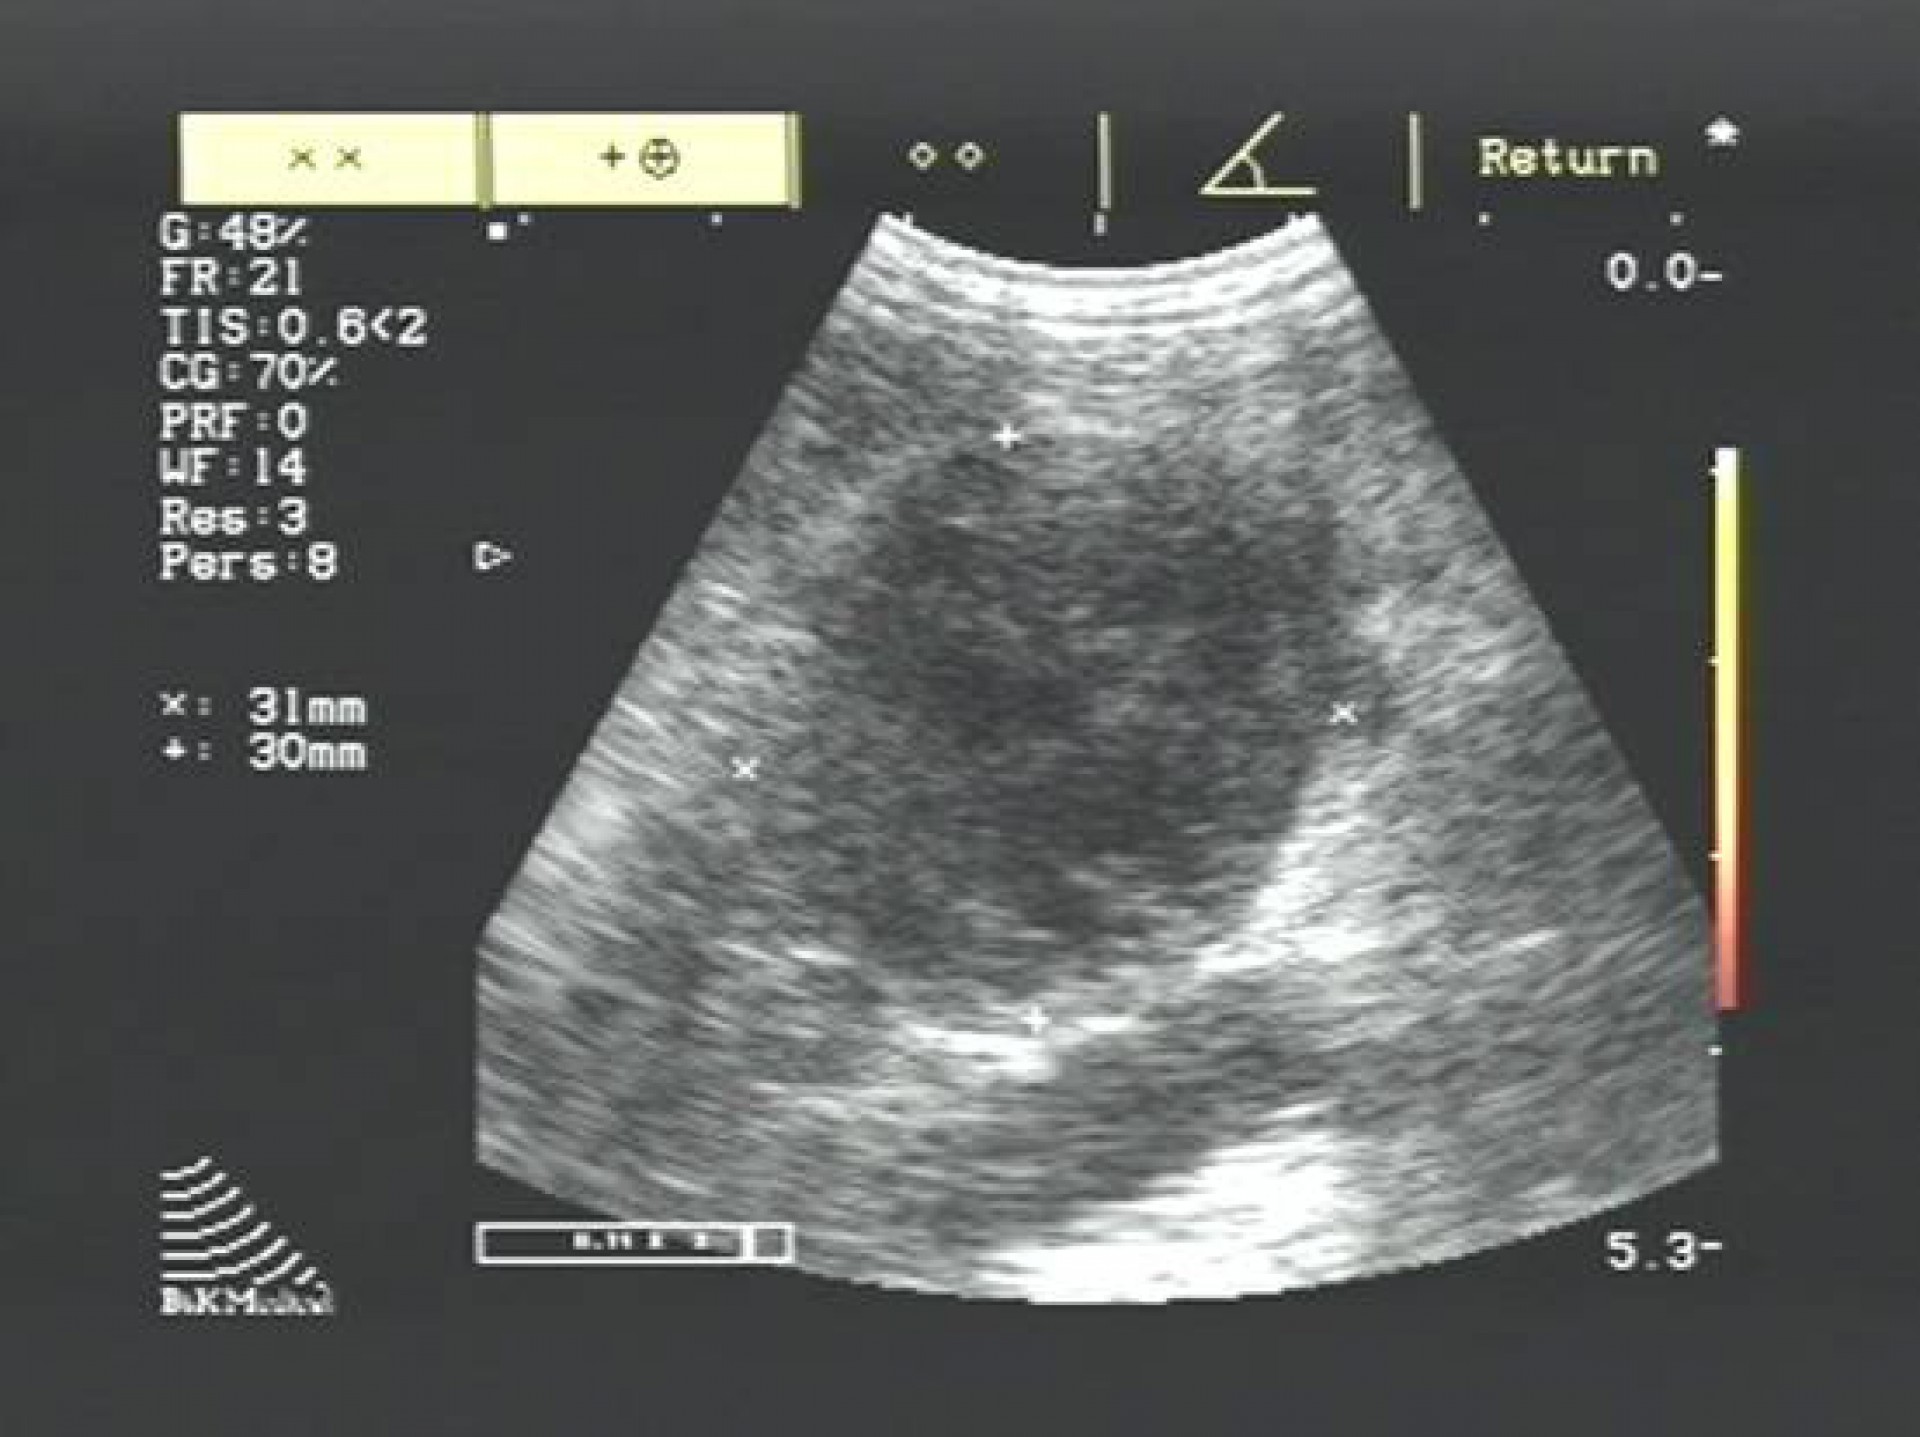

A betegség diagnosztizálása hasüregi ultrahangos vizsgálattal és vérvizsgálattal történik, mely során különös figyelmet kell fordítani a perifériás és centralis forma elkülönítésére.

Perifériás forma esetén amennyiben megbizonyosodtunk róla, hogy melyik oldali mellékvese elváltozása okozza a klinikai tüneteket, a betegség a daganatos mellékvese műtéti eltávolításával gyógyítható.